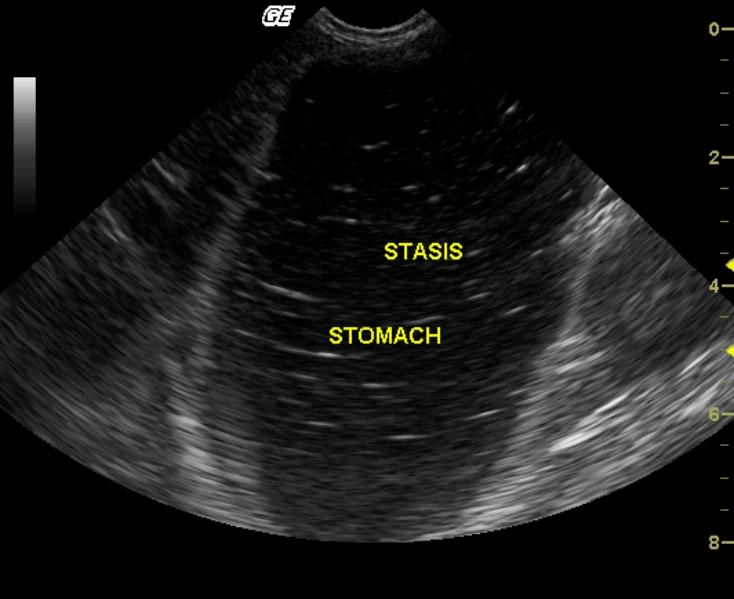

This 4-year-old MN Himalayan cat was presented for 3 days of persistent vomiting, lethargy, and anorexia. The physical exam revealed moderate dehydration and tense abdomen; the cat would not allow deep palpation. The CBC revealed moderate leukocytosis with a left shift. Blood chemistry demonstrated moderate azotemia, mild hyperglycemia, mild hyponatremia and hypochloremia. The urine was concentrated with minor proteinuria.